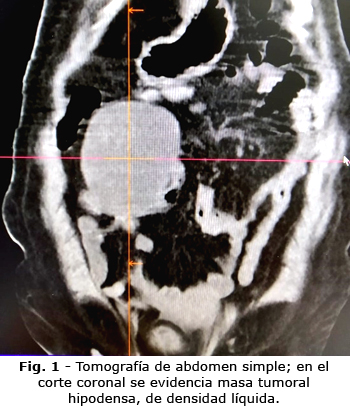

En los estudios de imagen resultó:

En la tomografía, el material olvidado está bien definido, rodeado por una pared densa visible o no, con contraste intravenoso. Frecuentemente tiene una apariencia arremolinada, por gas atrapado en la red de fibras textiles. También es posible demostrar niveles de fluidos o gas, indicando un absceso. En casos de larga duración, el material textil puede calcificarse.(7)